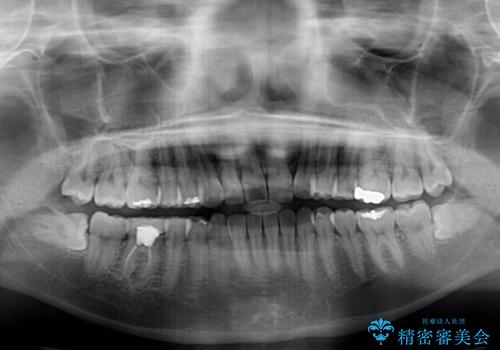

- 矯正治療の後戻りが気になるとのことで来院された患者様です。

上顎の後戻りをインビザライン・ライトで治療することとしました。

上顎のみの治療を希望されたため、咬み合わせをしっかりと改善することはできませんでしたが、審美面が大きく改善され、日常生活の機能面でも不具合を感じることはなく、大変満足していただきました。